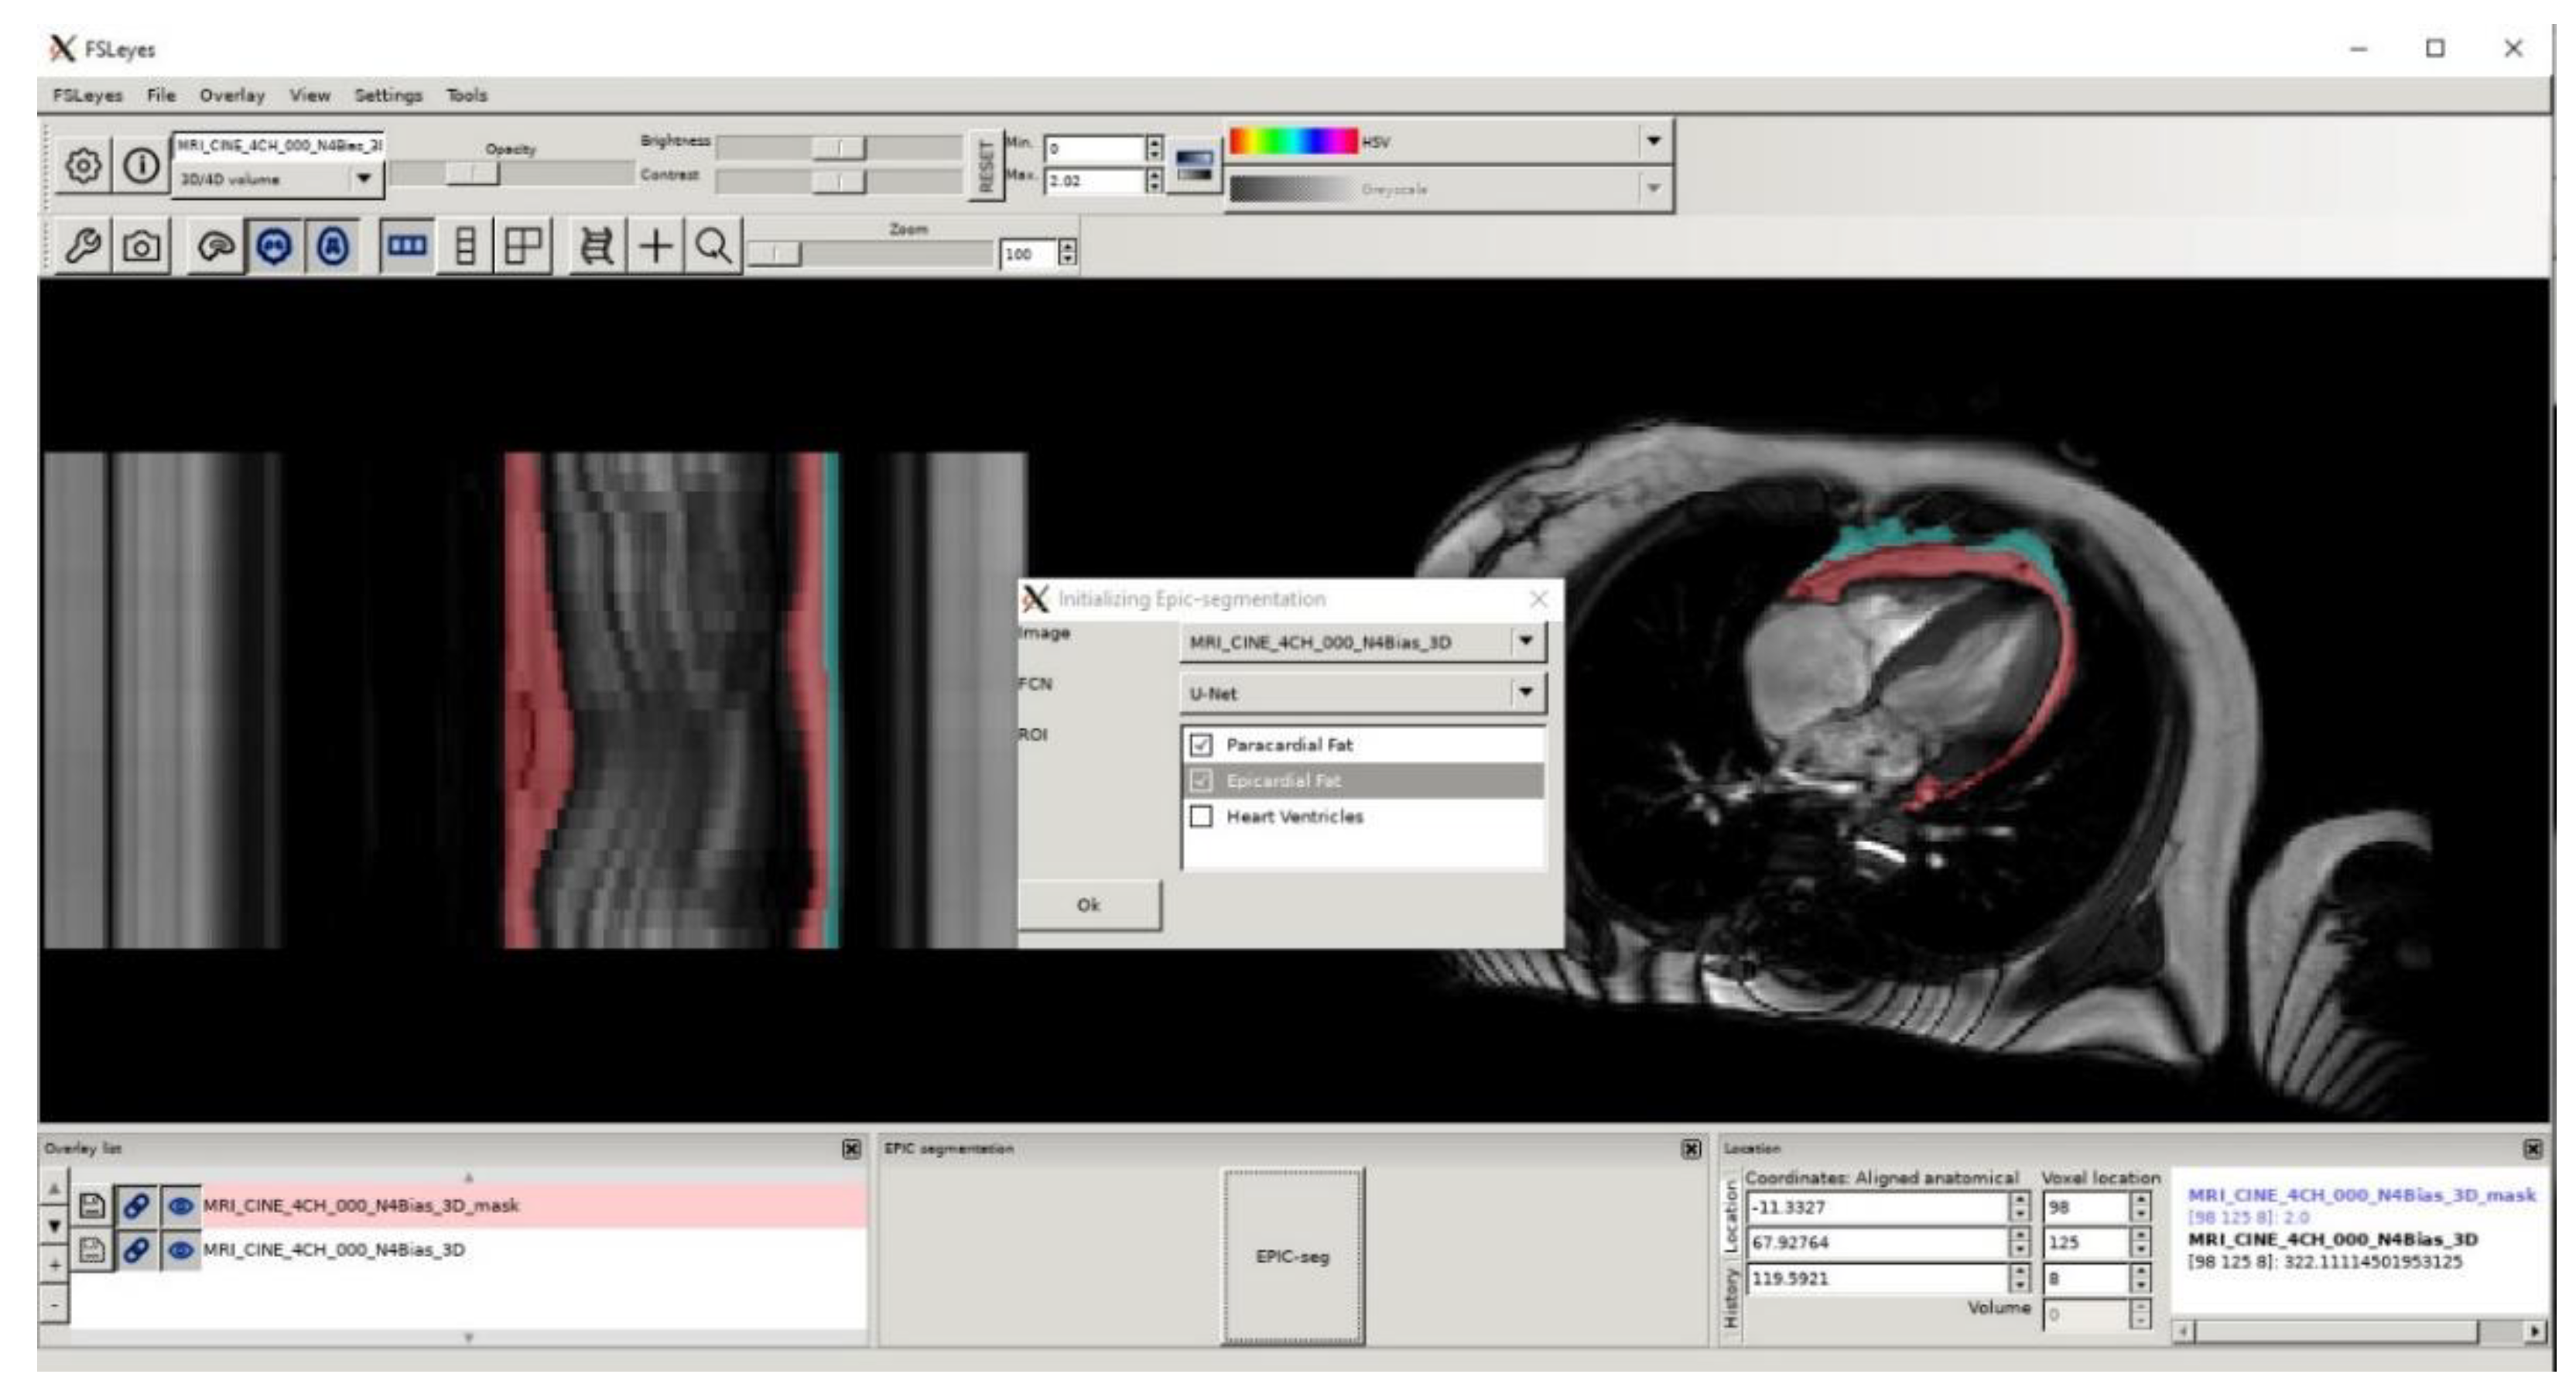

- McCarthy, Paul FSLeyes v.0.31. Available online: https://doi.org/10.5281/zenodo.3403671 (accessed on 2 October 2020).

- Daudé, P. Fsleyes-Plugin-Epicseg. Available online: https://github.com/pdaude/fsleyes-plugin-epicseg (accessed on 20 July 2021).